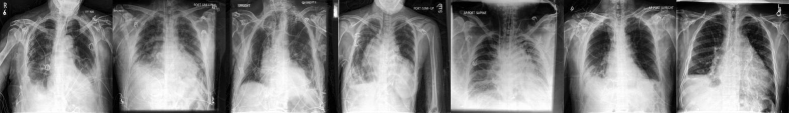

The second setting that we consider is radiology. We focus our analysis on two large public radiology datasets, CheXpert (Irvin et al., 2019) and ChestX-ray14 (US National Institutes of Health (NIH)) (Wang et al., 2017). These datasets have been widely studied by the community (Rajpurkar et al., 2017; Larrazabal et al., 2020; Seyyed-Kalantari et al., 2021) for model development and fairness analyses. For these datasets, demographic attributes like sex and age are publicly available, and classification is performed at a higher resolution, i.e. 224×224224224224\times 224 like in Azizi et al. (2022). After training the generative model and classifier on 201,055 examples of chest X-rays from the CheXpert dataset, we evaluate on a held-out CheXpert test set (containing 13,332 images), which we consider in-distribution, and the test set of ChestX-ray14 (containing 17,723 images), which we consider out-of-distribution (OOD) due to demographic and acquisition shifts. We focus on five conditions for which labels exist in common between the two datasets222Note that the labelling procedures for the two datasets were defined and enacted separately, which likely increases the complexity of the task., i.e., atelectasis, consolidation, cardiomegaly, pleural effusion and pulmonary edema, while each of these datasets contains more conditions (not necessarily overlapping), as well as examples with no findings, corresponding to healthy controls. In this setting the model backbone is shared across all conditions, while a separate (binary classification) head is trained for each condition, given that multiple conditions can be present at once. Figure 4 illustrates how often different conditions co-occur in the training and evaluation samples. It is apparent that capturing the characteristics of a single condition can be challenging given that in most cases they coexist with other conditions. One characteristic example is pleural effusion, which is included in the diagnosis of atelectasis, consolidation and edema in  50% of the cases. However, the scenario is slightly different for the OOD ChestX-ray14 dataset, where for most pairs of conditions the corresponding ratio is much lower. It is worth noting that the original CheXpert training set contains positive, negative, uncertain and unmentioned labels. The uncertain samples are not considered when learning the classification model, but they are used for training the diffusion model. The unmentioned label is considered a negative (i.e. the condition is not present) which yields a highly imbalanced dataset. Therefore, we report area under the receiver operating characteristic (ROC-AUC) curve in line with the CheXpert leaderboard, as raw accuracy is not very informative for such imbalanced settings.

We observe that synthetic images improve the average AUC for the five conditions of interest in-distribution, but even more so out-of-distribution. Improvements are particularly striking for cardiomegaly, where the model trained purely with synthetic images improves AUC by 21.1%percent21.121.1\% (see Figure G3). Overall, we observe an improvement of 5.2%percent5.25.2\% on average AUC OOD and a 44.6%percent44.644.6\% improvement in sex fairness gap (see Figure 5). We show some examples of generated augmentations by the diffusion model for a model conditioned on the diagnostic label in Figure G1. Higher resolution images are generated in comparison to histopathology with the use of a cascaded diffusion model that upsamples images generated at 64×64646464\times 64 resolution to 224×224224224224\times 224.